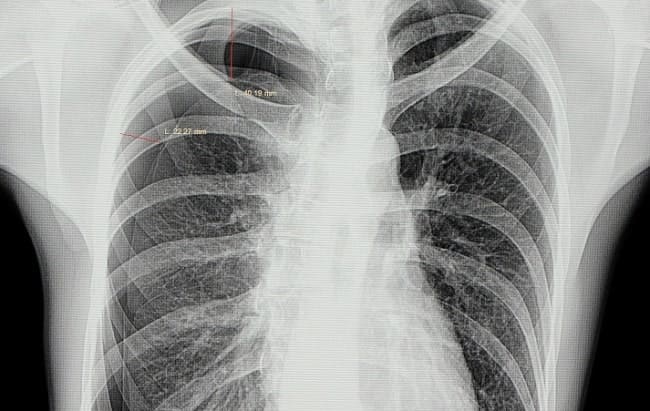

Walaupun pemeriksaan radiologis, seperti Rontgen toraks dan CT scan, membantu menegakkan diagnosis tetapi pneumotoraks merupakan diagnosis klinis yang didasarkan pada manifestasi pada pasien. Beberapa peneliti dan stake holder, seperti European task force, setuju bahwa evaluasi klinis dan manajemen pneumotoraks spontan primer seharusnya dilakukan berdasarkan klinis pasien, bukan berdasarkan temuan pada Rontgen toraks atau CT scan.[2]

Sejalan dengan ini, American College of Chest Physician (ACCP) juga mengategorikan rekomendasi terapi berdasarkan beratnya gejala dan tingkat keparahan kolaps paru yang dinilai dengan Rontgen toraks. Pasien dengan klinis yang stabil dapat diobservasi selama 3–6 jam di unit gawat darurat dan pasien dapat dipulangkan apabila hasil Rontgen toraks tidak mengindikasikan progresivitas pneumotoraks.